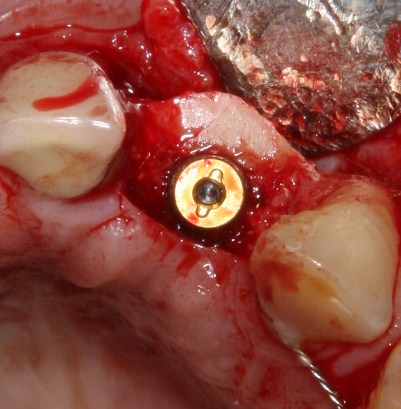

Делаем разрез, скелетируем костную ткань:

Как видите, коллагеновая мембрана полностью резорбировалась, а костный блок прижился и интегрировался на челюстной кости. Можно убрать винты:

и приступить к подготовке лунки под имплантат:

По существующим правилам, при установке импланта в области фронтальной группы зубов, его ось должна выходить на небную поверхность коронки или режущий край. Чего мы и добиваемся, контролируя процесс с помощью пинов.

Я планирую установить имплантат Dentsply Friadent XiVE диаметром 3.8 и длиной 13 мм. Это оптимальный размер импланта для протезирования боковых резцов.

Установка импланта:

Убираем имплантодержатель. Обратите внимание, что полированная фаска вокруг шейки импланта находится над уровнем костной ткани. Чрезмерное погружение импланта — весьма распространенная имплантологическая ошибка.

Заглушка: